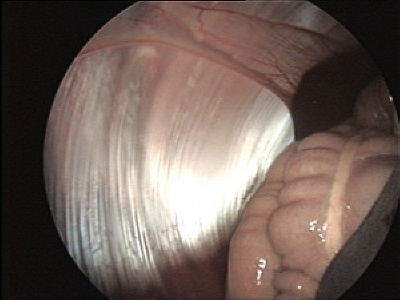

Laparoskopie